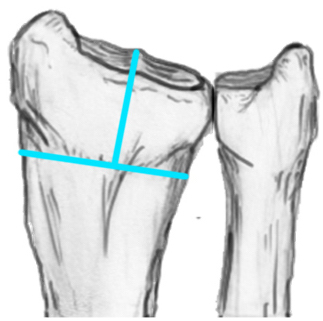

Radial angles

| Volar tilt mean 11° | Radial inclination mean 22° | Radius mean 11 mm longer than ulna |